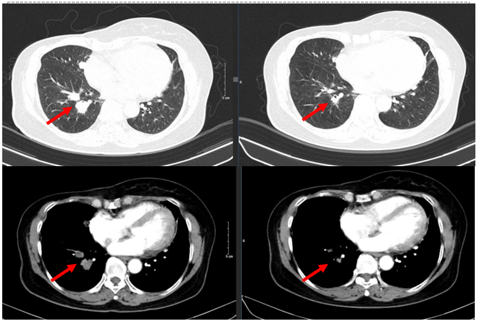

Hình 2. Hình ảnh chụp CT ngực trước điều trị: Tổn thương phổi 2 bên

Hình 5. Hình ảnh chụp CT ngực trước và sau điều trị: Tổn thương phổi trái

Hình 6. Hình ảnh chụp CT ngực trước và sau điều trị: Tổn thương phổi phải

Phổi phải: nhu mô thuỳ giữa và dưới có các khối – nốt đặc, lớn nhất 7x8mm

+ Phổi trái: nhu mô thuỳ trên và đáy phổi sát màng phổi có các khối nốt đặc, lớn nhất 9x8mm